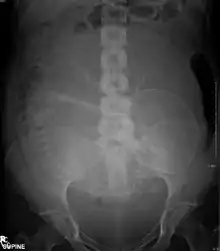

Projectional radiography is the practice of producing two-dimensional images using X-ray radiation. Bones contain a high concentration of calcium, which, due to its relatively high atomic number, absorbs X-rays efficiently. This reduces the amount of X-rays reaching the detector in the shadow of the bones, making them clearly visible on the radiograph. The lungs and trapped gas also show up clearly because of lower absorption compared to tissue, while differences between tissue types are harder to see.

Projectional radiographs are useful in the detection of pathology of the skeletal system as well as for detecting some disease processes in soft tissue. Some notable examples are the very common chest X-ray, which can be used to identify lung diseases such as pneumonia, lung cancer, or pulmonary edema, and the abdominal X-ray, which can detect bowel (or intestinal) obstruction, free air (from visceral perforations), and free fluid (in ascites). X-rays may also be used to detect pathology such as gallstones (which are rarely radiopaque) or kidney stones which are often (but not always) visible. Traditional plain X-rays are less useful in the imaging of soft tissues such as the brain or muscle. One area where projectional radiographs are used extensively is in evaluating how an orthopedic implant, such as a knee, hip or shoulder replacement, is situated in the body with respect to the surrounding bone. This can be assessed in two dimensions from plain radiographs, or it can be assessed in three dimensions if a technique called '2D to 3D registration' is used. This technique purportedly negates projection errors associated with evaluating implant position from plain radiographs.[101]